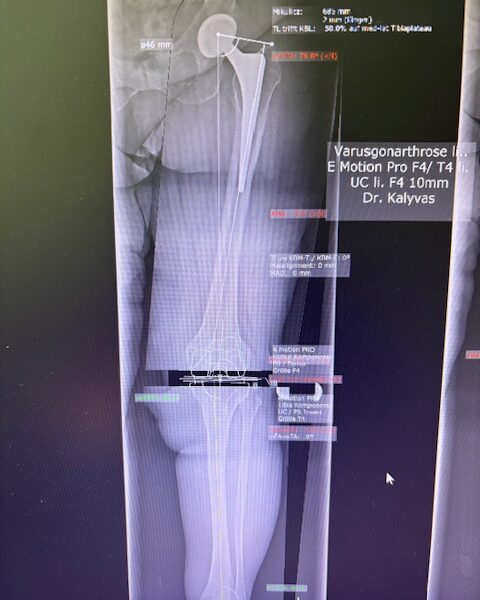

Ο προεγχειρητικός ψηφιακός σχεδιασμός

Πραγματοποιήθηκε σε ειδική ακτινογραφία ολόκληρων των δύο κάτω άκρων. Σε αυτό το ψηφιακό μοντέλο σχεδιάστηκε με ακρίβεια το είδος, το μέγεθος και η ακριβής θέση των προθέσεων, με βάση τα ανατομικά χαρακτηριστικά της ασθενούς.

Ο ψηφιακός σχεδιασμός επιτρέπει απόλυτη εφαρμογή των μοσχευμάτων, ελαχιστοποιώντας τα περιθώρια απόκλισης και εξασφαλίζοντας άριστη ευθυγράμμιση και κινηματική ισορροπία του γόνατος.

Τα εμφυτεύματα που χρησιμοποιήθηκαν στο γόνατο της ασθενούς είναι της Aesculap: E-Motion Pro, μηριαίο μέγεθος 4, κνημιαίο μέγεθος 4, με ενθέμα (inlay) 10mm.